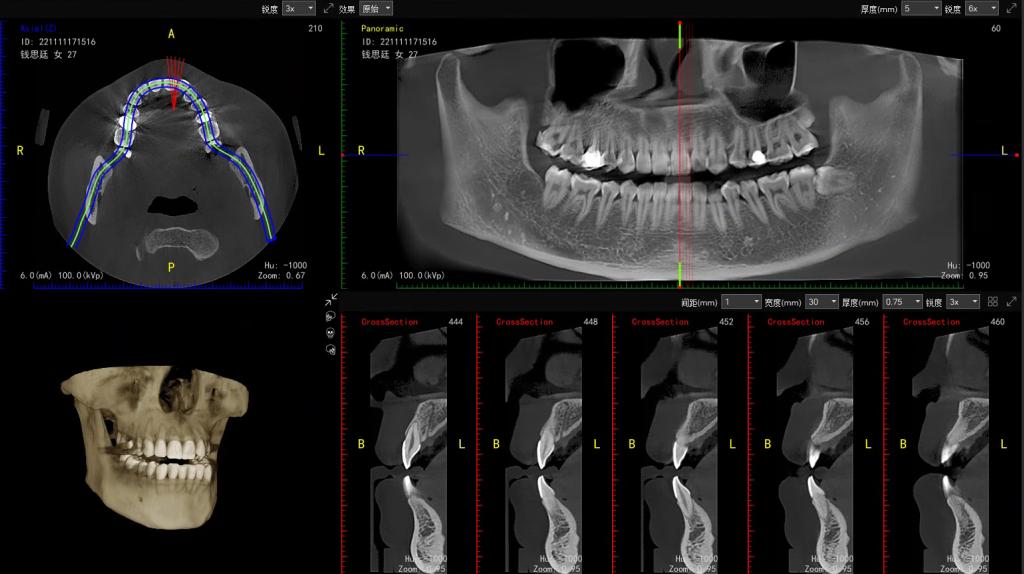

(二)口腔全景及口腔 CT专项服务

为口腔疾病诊断、种植牙规划、正畸治疗提供精准解剖定位;

1.牙齿基础病变排查:精准识别龋坏、残根、牙齿缺失,以及牙周炎、牙周脓肿等牙周组织病变,为基础牙科治疗提供影像依据。

2.智齿与阻生牙评估:清晰显示智齿生长位置、萌出状态,判断阻生牙对邻牙的压迫情况、是否存在埋伏阻生等,为智齿拔除手术方案制定提供支持。

3.牙齿矫正规划:全面呈现牙列排列、牙槽骨形态、颌骨关系等核心数据,助力正畸医生制定个性化矫正方案,实时监测矫正过程中牙齿及颌骨的变化。

优势:口腔全景片与口腔 CT的辐射剂量均处于极低水平,安全性高,无需过度担心。